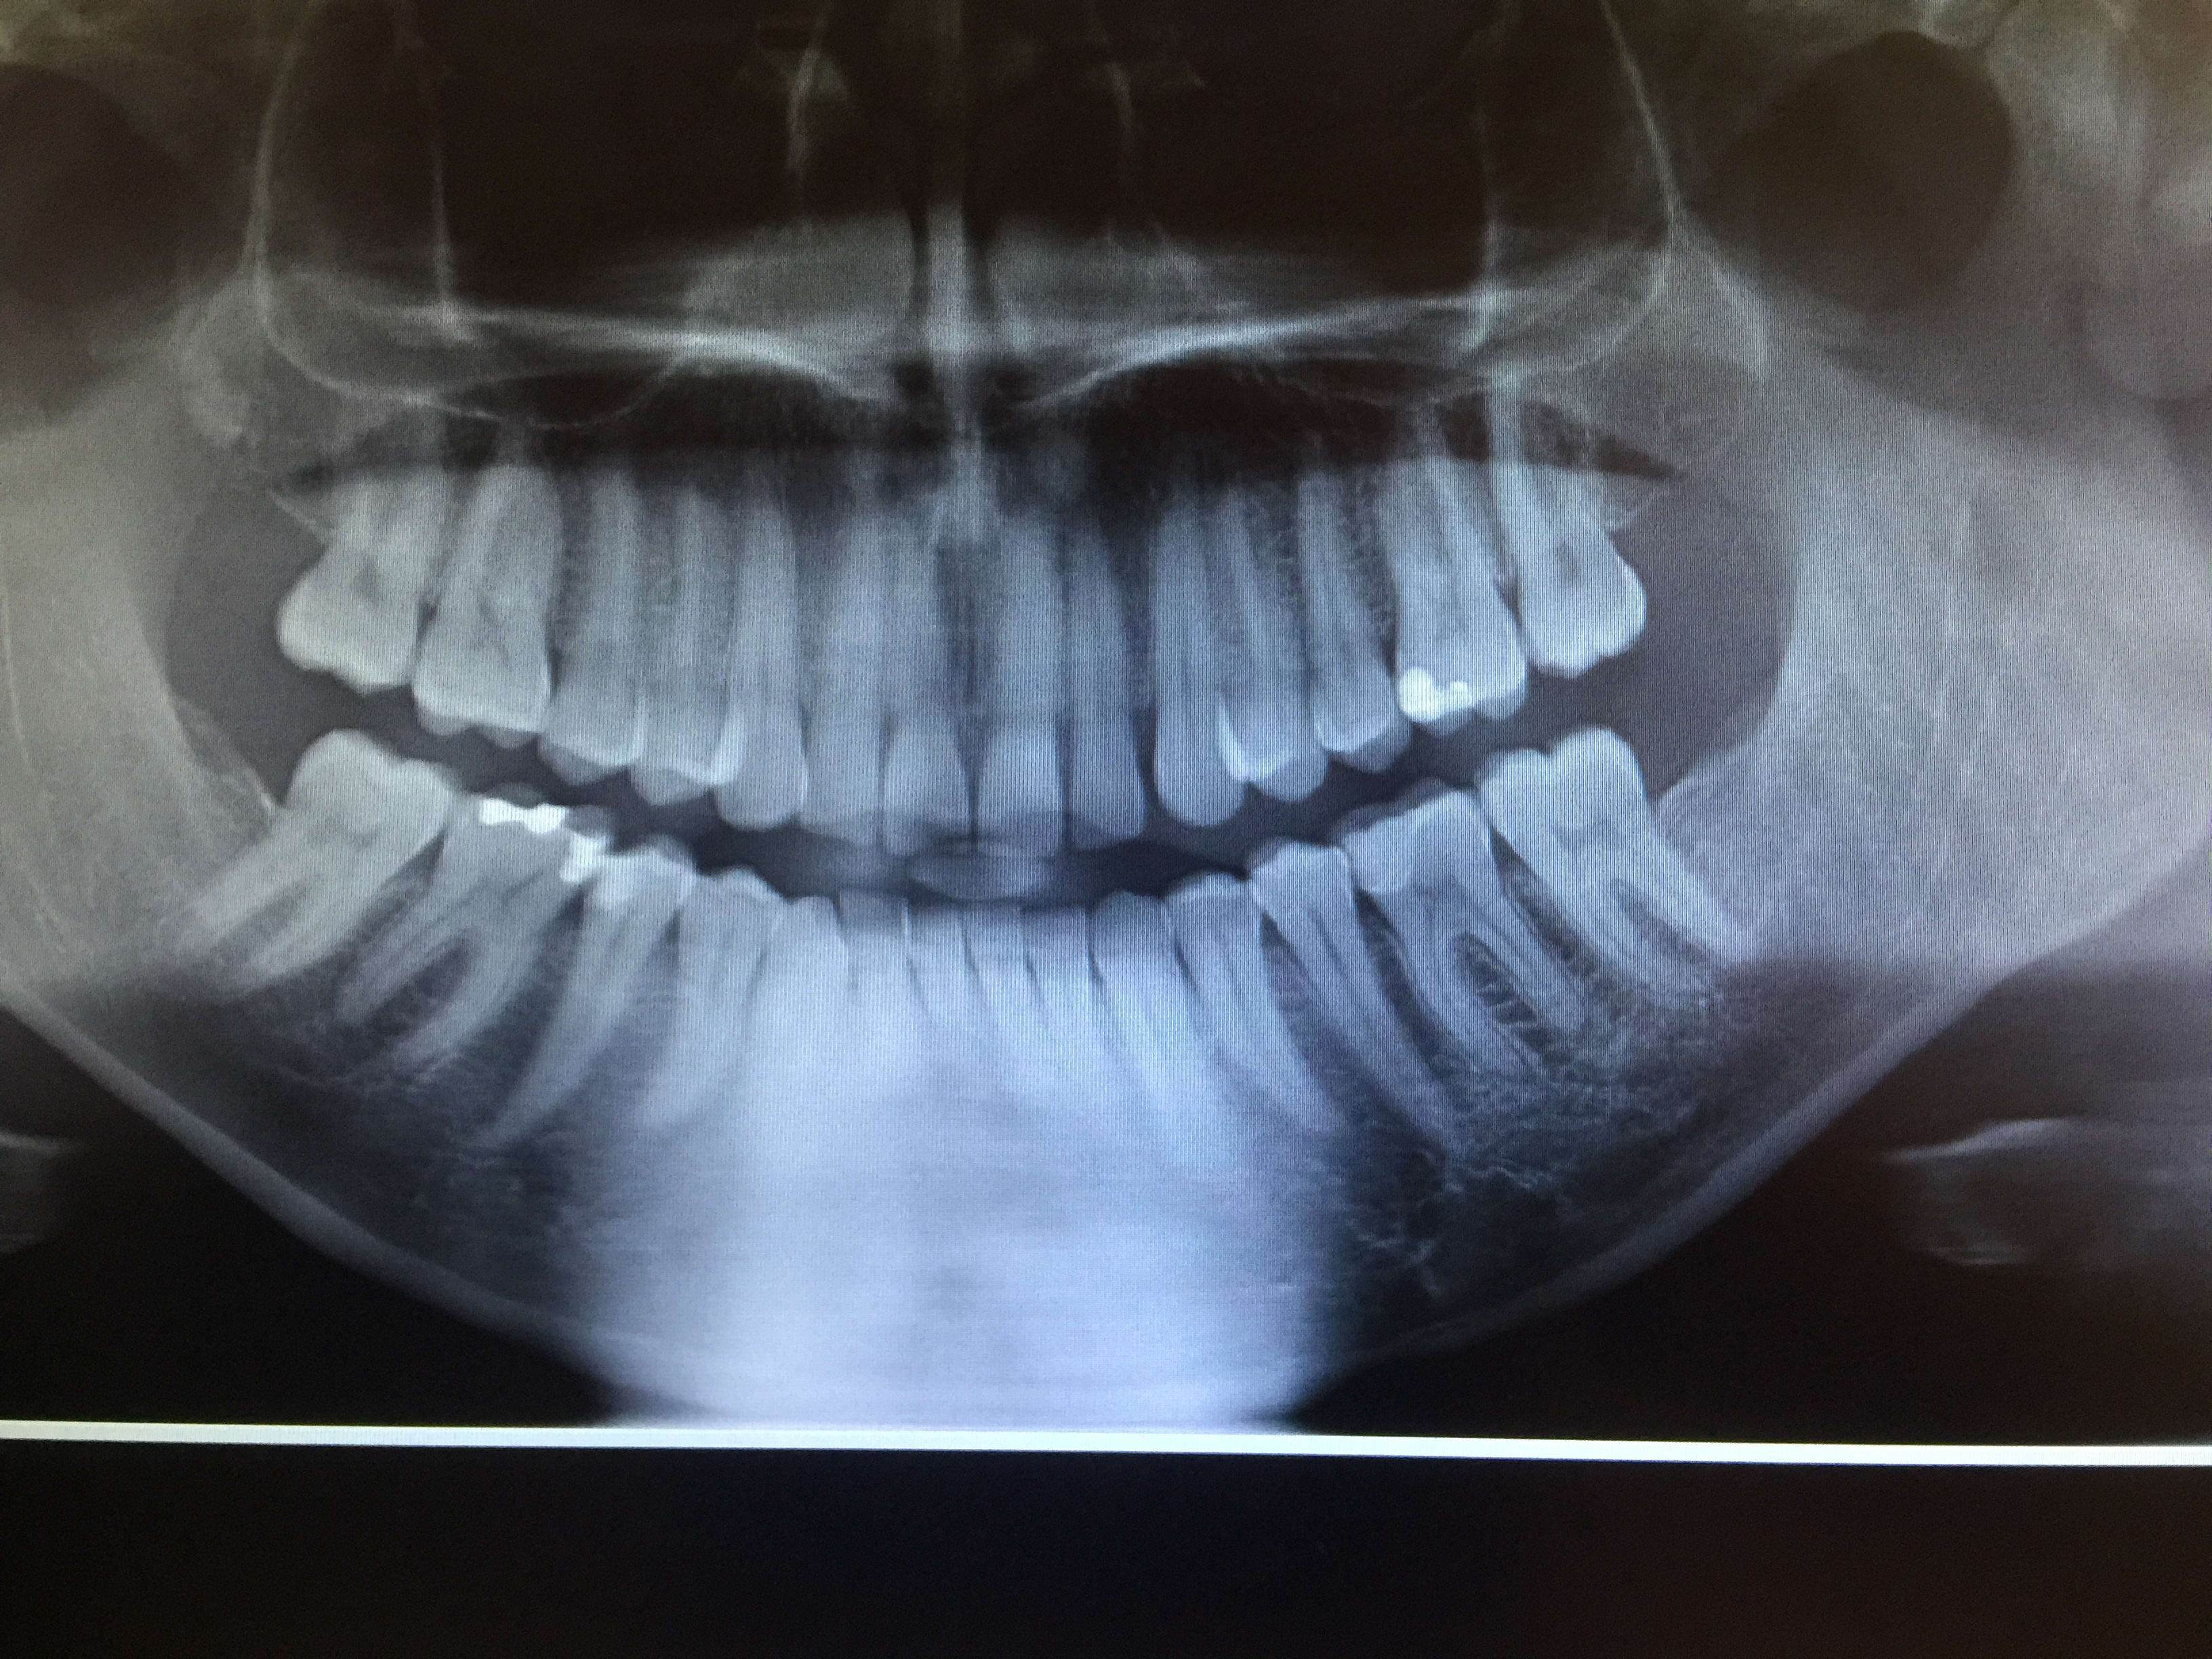

Qu'est-ce que vous pensez de l'image en dessous de la 35?

trou mentonnier un peu large....